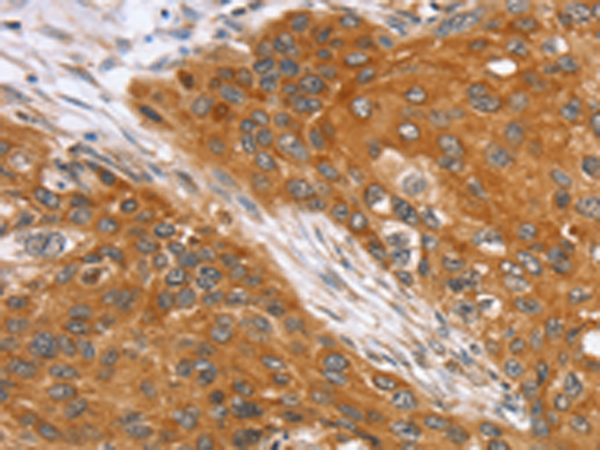

分类: 科研抗体货号: P08760别名: TID1; HCA57; hTID-1应用: IHC反应种属: Human, Mouse